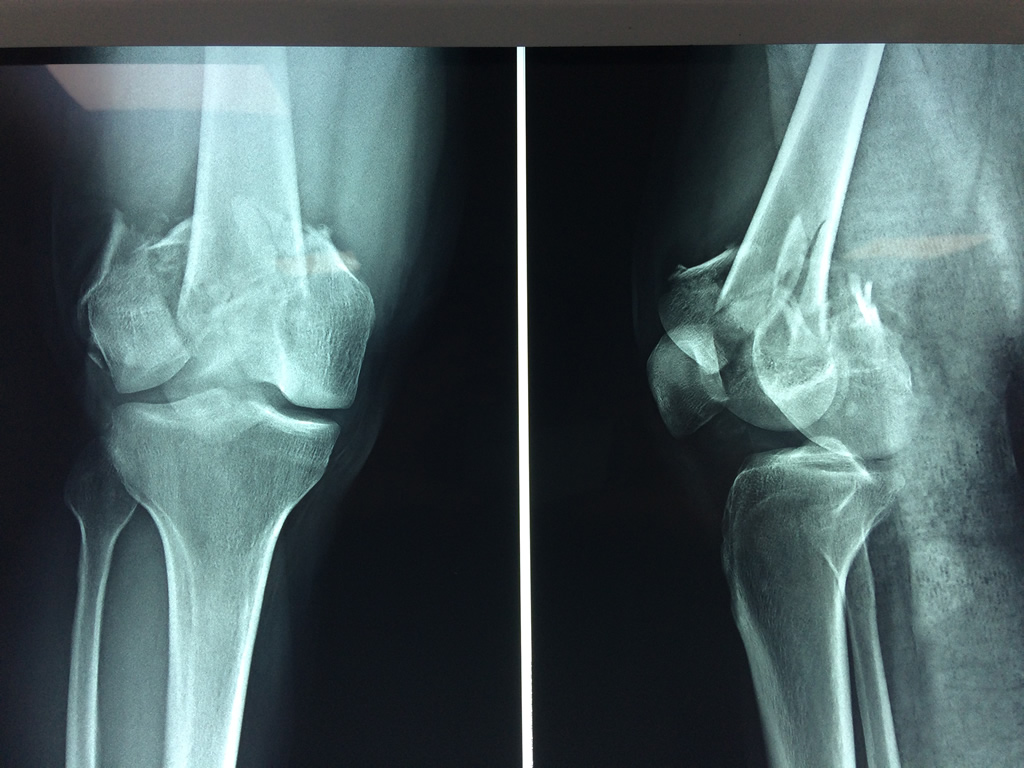

Cirugías de Calcaneo - Fémur

El fémur es el hueso del muslo, el segundo segmento del miembro inferior. Es el hueso más largo, fuerte y voluminoso del cuerpo humano.